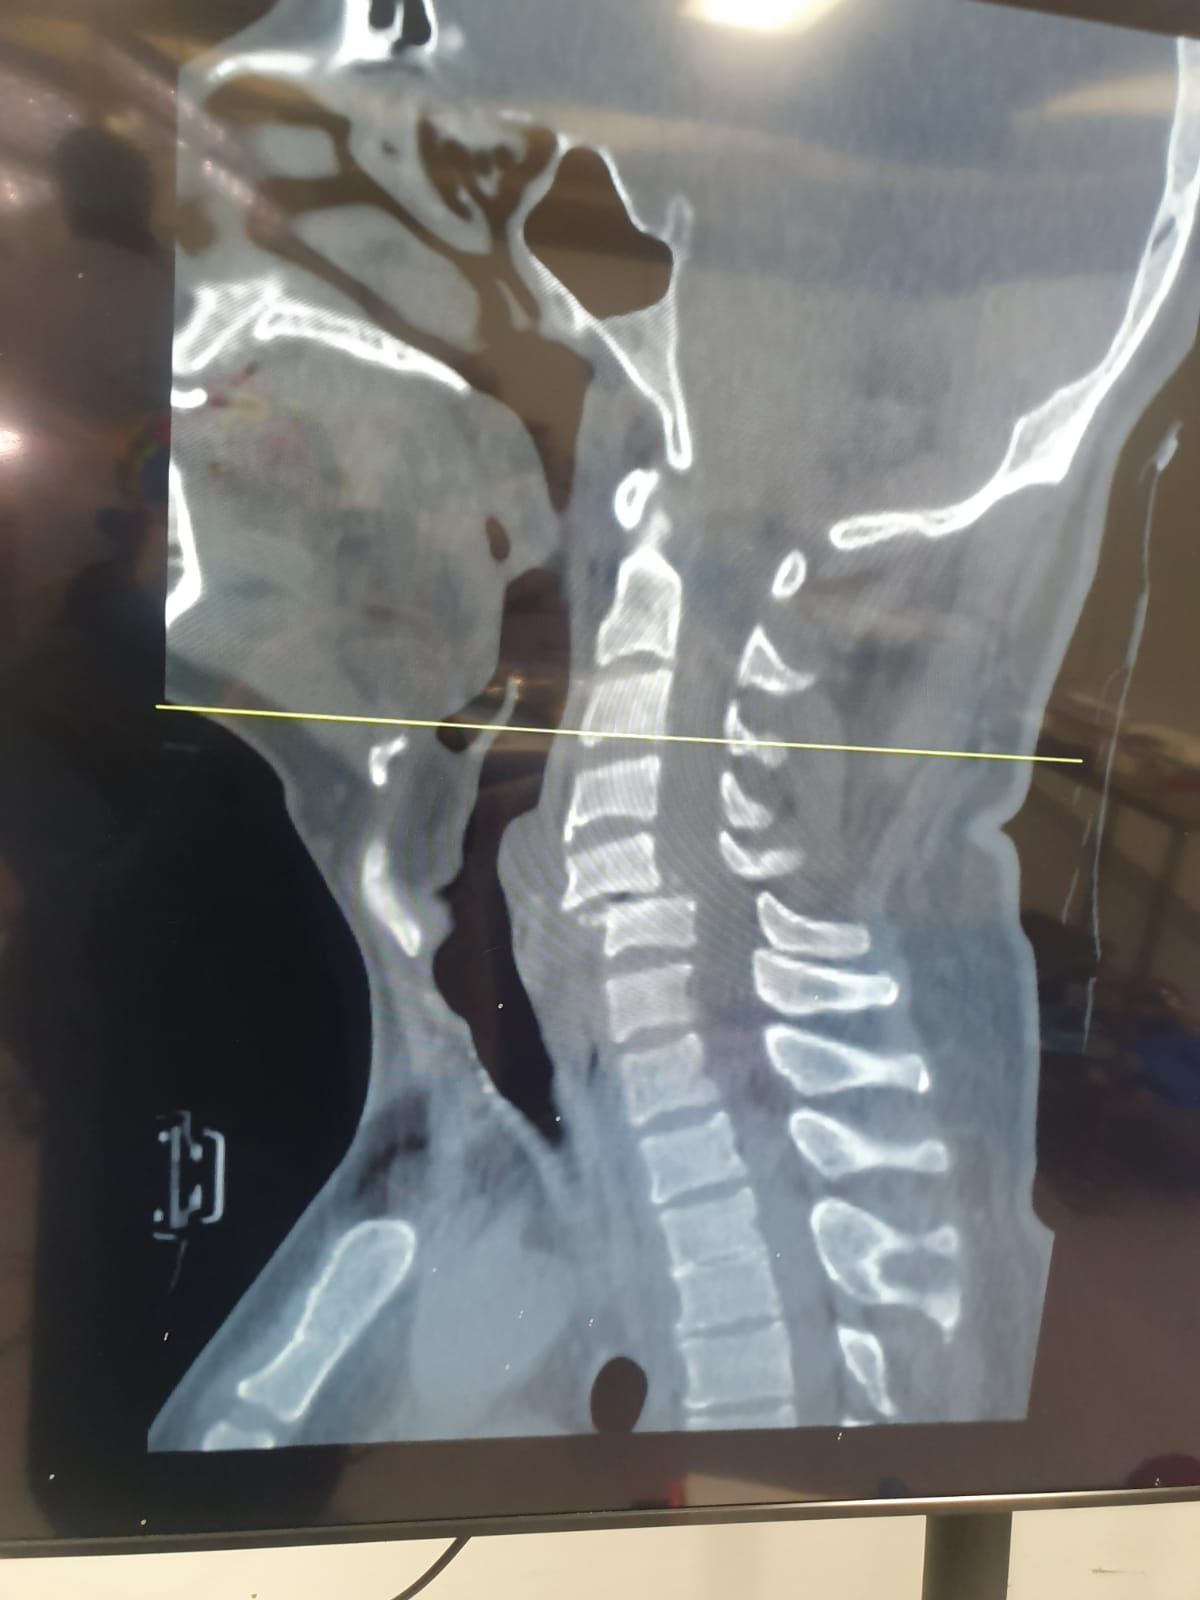

Fracturas Vertebrales

Fracturas por osteoporosis, trauma o lesiones patológicas. Requieren estabilización quirúrgica para prevenir complicaciones neurológicas.

La columna vertebral es una estructura compleja que protege la médula espinal y permite el movimiento del cuerpo. Está compuesta por 33 vértebras divididas en regiones: cervical (cuello), dorsal o torácica (espalda media), lumbar (espalda baja), sacra y coccígea.

Las patologías de la columna pueden causar dolor intenso, debilidad, entumecimiento y pérdida de función. El tratamiento quirúrgico está indicado cuando el tratamiento conservador no ha sido efectivo o cuando existe compromiso neurológico.

Vértebras Cervicales

Vértebras Dorsales

Vértebras Lumbares

Vértebras Totales

Compresión de la Médula Espinal

¿Qué es?

La compresión medular es una emergencia neuroquirúrgica donde la médula espinal es comprimida por hernias masivas, tumores, fracturas o hematomas. Requiere intervención urgente para evitar daño neurológico permanente.

Descompresión medular urgente mediante laminectomía o corpectomía, eliminando la causa de compresión. En fracturas se realiza estabilización con instrumentación. La cirugía debe realizarse en las primeras 24-48 horas para mejores resultados.

Pronóstico: La recuperación neurológica depende del tiempo de evolución previo a la cirugía. La intervención temprana ofrece las mejores posibilidades de recuperación funcional completa.